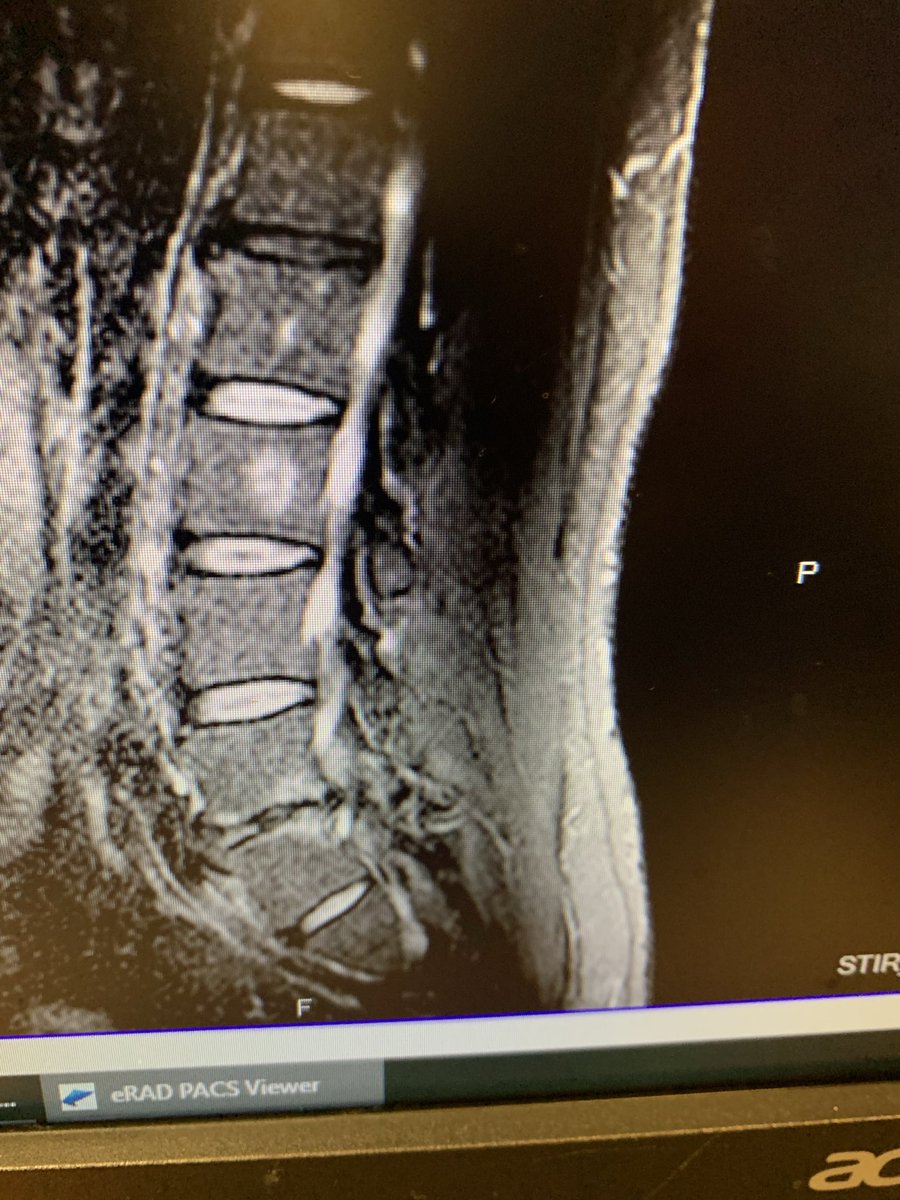

@JayGlazer @TheAuragens No plates or screws?